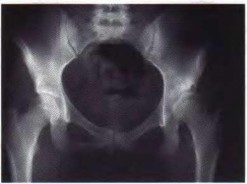

Question 39:

An 18-year-old pedestrian is struck by a motor vehicle and sustains a severe pelvic ring injury. AP, inlet, and outlet radiographs suggest an Anteroposterior Compression (APC) mechanism. According to the Young-Burgess classification system, an APC Type III injury is fundamentally distinguished from an APC Type II injury by the complete disruption of which of the following specific structures?

Explanation:

In the Young-Burgess classification, Anteroposterior Compression (APC) injuries follow a progressive pattern of ligamentous disruption. APC I features symphyseal widening <2.5 cm with intact posterior ligaments. APC II features symphyseal widening >2.5 cm, complete disruption of the anterior sacroiliac, sacrospinous, and sacrotuberous ligaments, but crucially, the strong posterior sacroiliac ligaments remain INTACT, allowing the hemipelvis to open like a book (rotationally unstable but vertically stable). APC III involves complete disruption of both the anterior and posterior sacroiliac ligaments, completely dissociating the hemipelvis from the sacrum (both rotationally and vertically unstable).